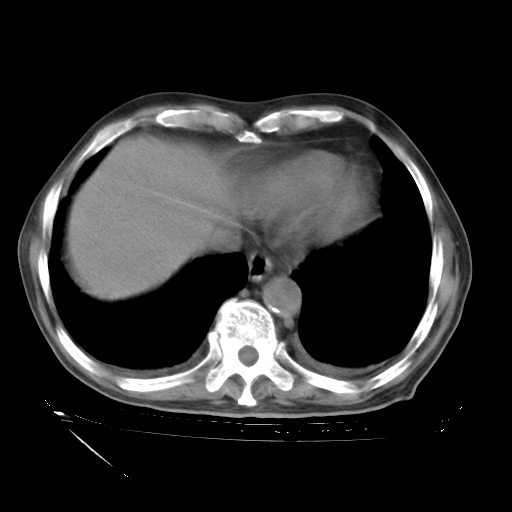

甲强龙80mg/日+抗结核治疗(异烟肼+利福霉素+乙胺丁醇)10天。复查肺部CT。

治疗10天肺部CT